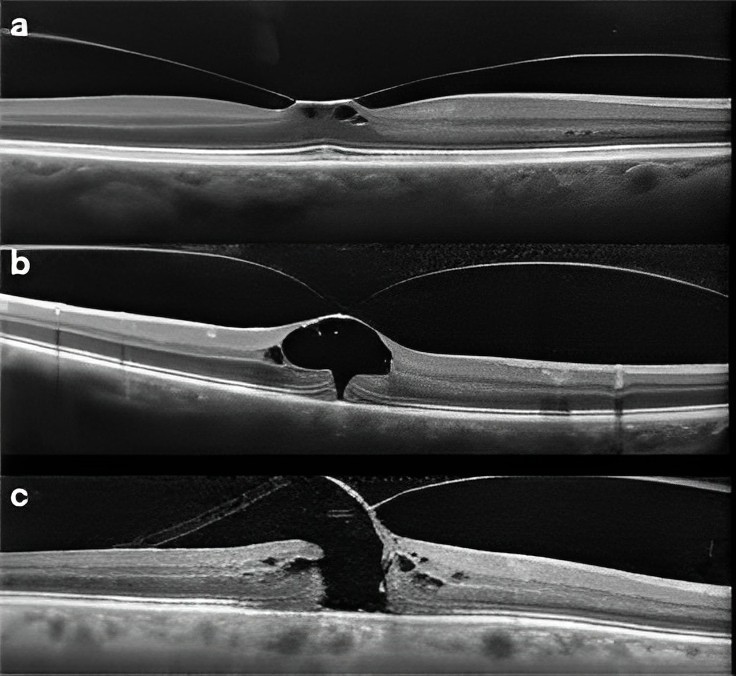

Vitreomaküler traksiyon (VMT), göz küresinin arka kısmını dolduran vitreus jeli ile retina arasındaki anormal bağlantıdan kaynaklanan bir göz hastalığıdır. Bu bağlantı, vitreus jelinin yaşlanma veya diğer faktörler nedeniyle retinadan ayrılırken oluşur. VMT, görme keskinliğinde azalmaya, görme alanında kayıplara ve makula hasarına yol açabilir. 30 yaş üstü kişilerde daha sık görülür.

Vitreomaküler traksiyon (VMT) ameliyatı, vitreus jeli ile retina arasındaki anormal bağlantıyı düzeltmek için yapılan bir göz ameliyatıdır. Ameliyat mikroskop altında lokal veya genel anestezi altında yapılır.